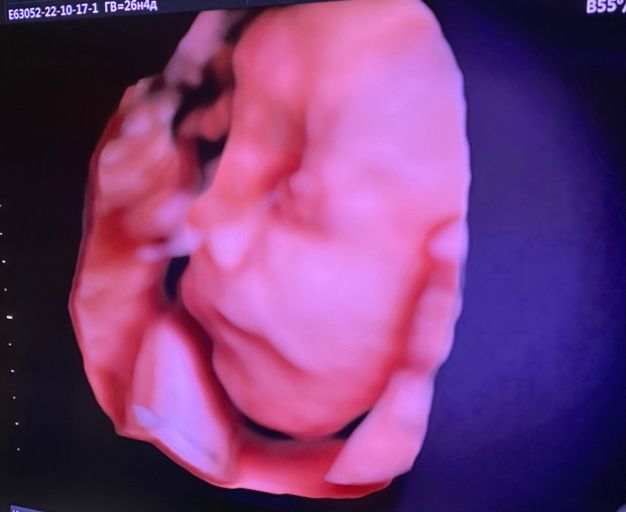

32 недели ☺️